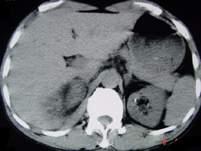

问题 男,25岁,右腰部疼痛伴血尿,有外伤史,CT扫描如图所示,应诊断为 ( )

选项 A、右肾梗死 B、右肾脓肿 C、右肾血管平滑肌瘤 D、右肾癌 E、右肾挫伤并包膜下血肿

答案 E